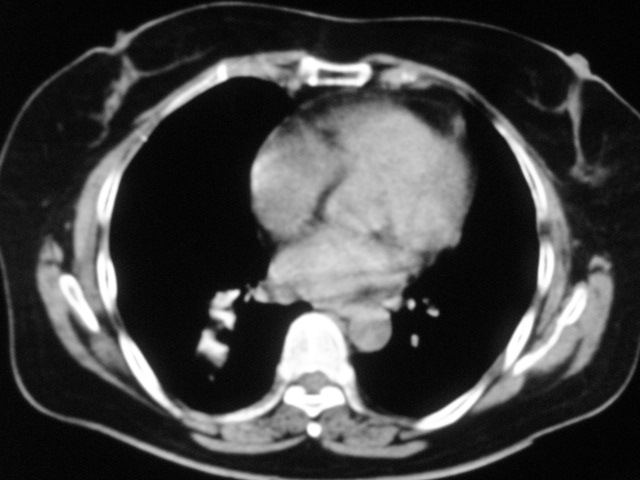

以下是引用清清楚楚在2007-8-28 7:13:00的发言:[br]右肺下叶可见斑片状高密度影,边缘模糊;右肺中叶内侧段及左肺舌段亦可见小斑片状模糊影。[br]考虑双肺感染,建议抗炎治疗后复查。

以下是引用天南地北在2007-8-27 23:49:00的发言:[br]右肺下叶可见斑片状高密度影,边缘模糊;右肺中叶内侧段及左肺舌段亦可见小斑片状模糊影。[br]考虑双肺感染,建议积极抗炎治疗后复查。

以下是引用难听在2007-8-28 13:17:00的发言:[br]右肺下叶背段支气管狭窄,是否可以考虑新生物伴阻塞性肺炎.请大家帮帮忙,这个病人是卫生局长的丈母娘.惹不起啊.